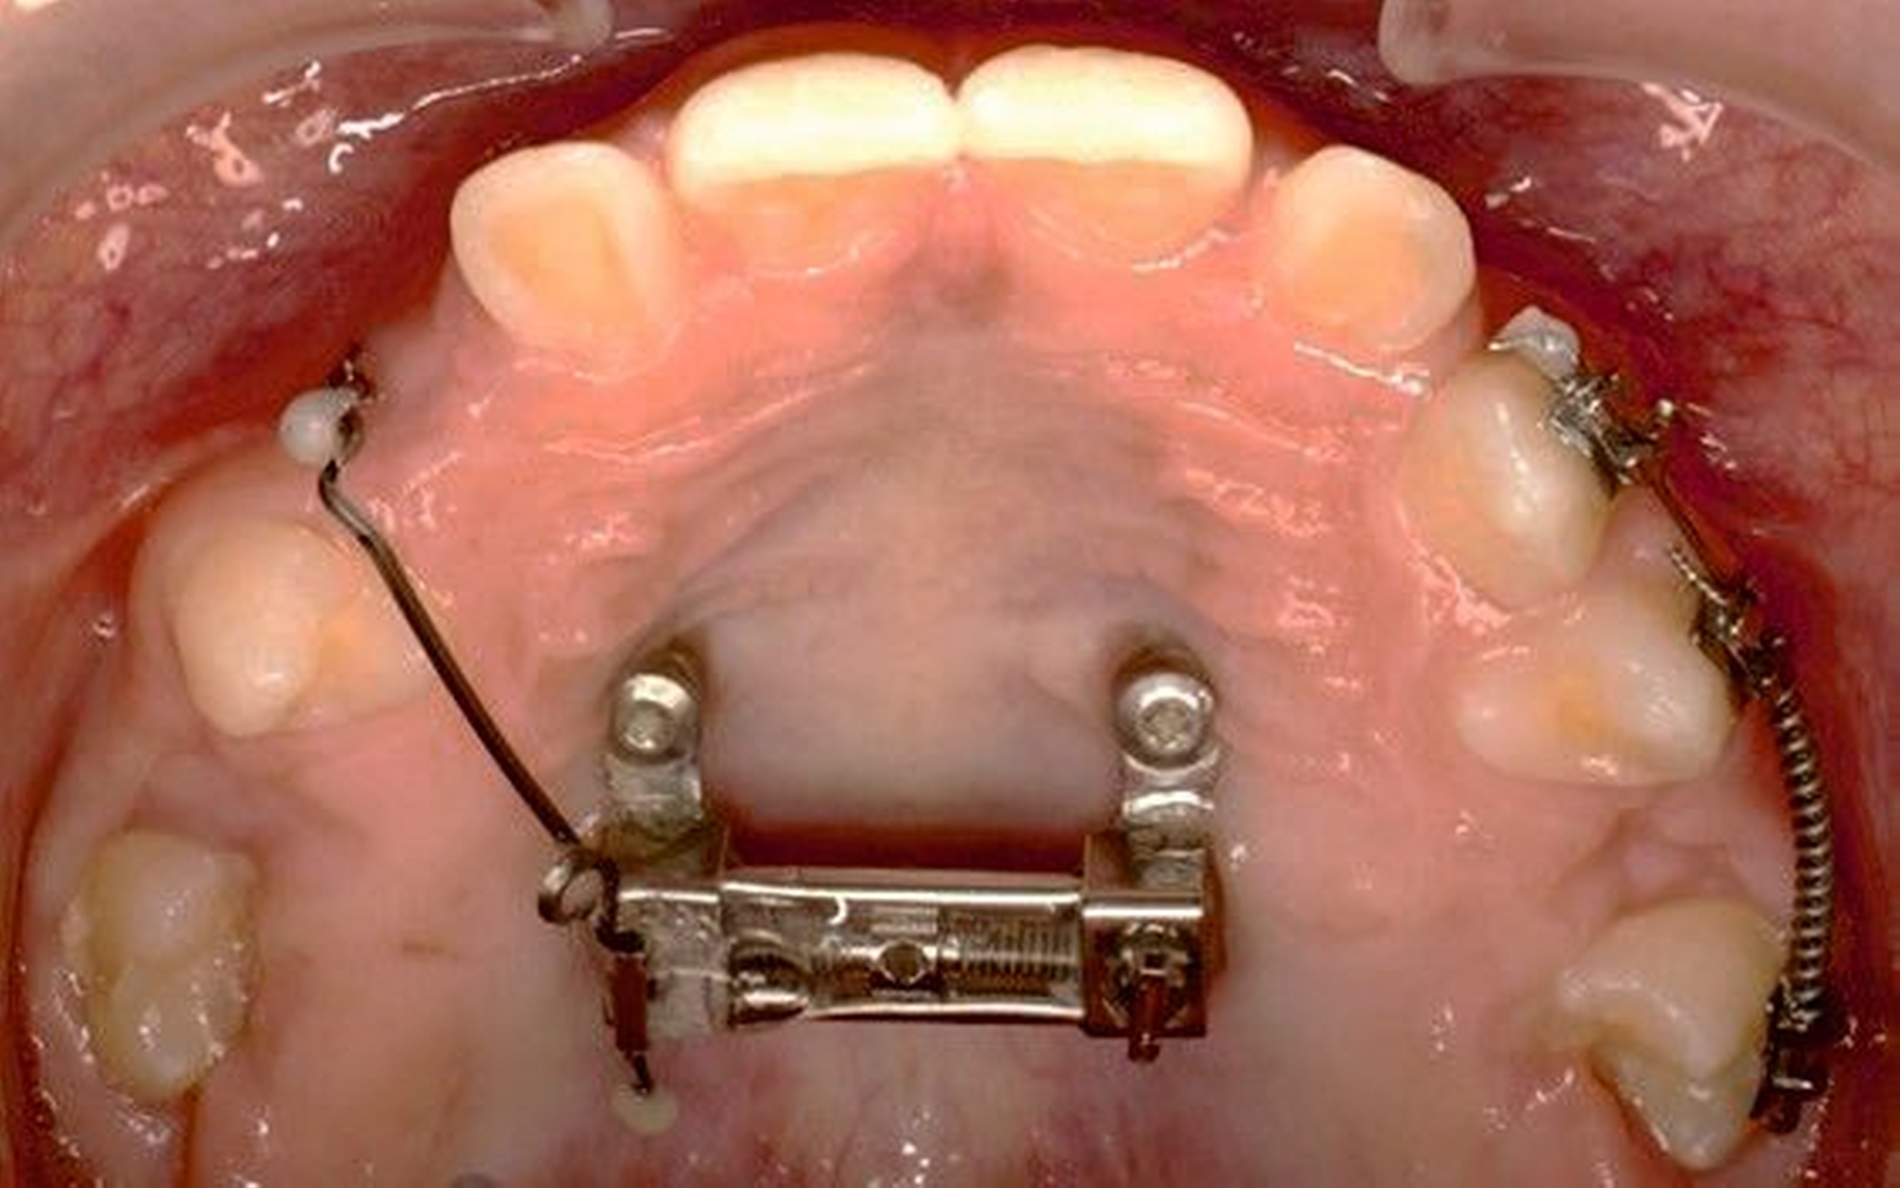

Die Eltern des Patienten wurden angewiesen, die Schraube einmal täglich zu aktivieren. Die gesamte Aktivierungszeit der Hyrax-Schraube betrug circa zehn Wochen. Während dieser Zeit vergrößerte sich die transversale Dimension des Oberkiefers um sieben Millimeter im posterioren Bereich (Milchmolaren) und um fünf Millimeter im anterioren Bereich (Milcheckzähne). Währenddessen trat ein mediales Diastema auf (Abbildungen 4b und 4c), das auf eine skelettale transversale Expansion des Oberkieferknochens hinwies. Nach der aktiven Expansionsphase der Hyrax-Apparatur wurde das Gerät für weitere Behandlungszwecke verwendet: Erstens als Retentionsgerät, um die bereits erzielte transversale Oberkieferbreite zu halten und zweitens als skelettal verankerte Apparatur zum Einstellen der retinierten und verlagerten Zähne mithilfe individuell angefertigter Kragarme. Hierfür wurde die Hyrax-Apparatur im zahntechnischen Labor modifiziert, indem Kreuzröhrchen für eine stationäre Befestigungen für die Drähte des Kragarms angebracht wurden.

Für die Zähne 13, 16, 23 und 26 wurde eine weitere chirurgische Freilegung durchgeführt. Zwei Kragarme (0,017 x 0,025 Zoll TMA-Draht, Dentaurum, Ispringen, Deutschland) wurden verwendet, um die Zähne 13 und 23 kieferorthopädisch in den Zahnbogen einzustellen. Danach wurde eine Teil-Multi-Bracket-Apparatur eingesetzt, um die eruptierten Zähne zu nivellieren (Abbildung 5b). Nach einer Behandlungsdauer von circa sechs Monaten waren die chirurgisch freigelegten Zähne optimal eingeordnet (Abbildungen 5c und 5d). Um die Lücke für die noch retinierten Prämolaren 15 und 25 zu öffnen, wurden in dieser Region auf den Teilbögen offene Federn angebracht. Danach wurden die Zähne 15 und 25 chirurgisch freigelegt und ebenfalls mithilfe von zwei Kragarmen (0,017 x 0,025 Zoll TMA-Draht) eingestellt (Abbildungen 5e und 5f, Abbildung 6).